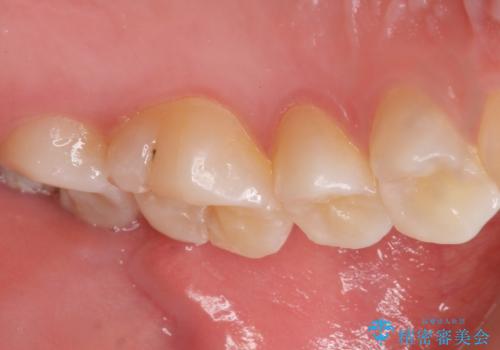

気づかなかった奥歯のう蝕 セラミックインレー 20代女性

- クリーニングを希望され来院された患者様です。

精査したところ、奥歯にう蝕を認めました。

症状がなく気がつかなかったそうで、虫歯があったことに驚かれていました。

患者様のご希望により、う蝕を丁寧に除去したのちセラミックインレーによる修復を行いました。